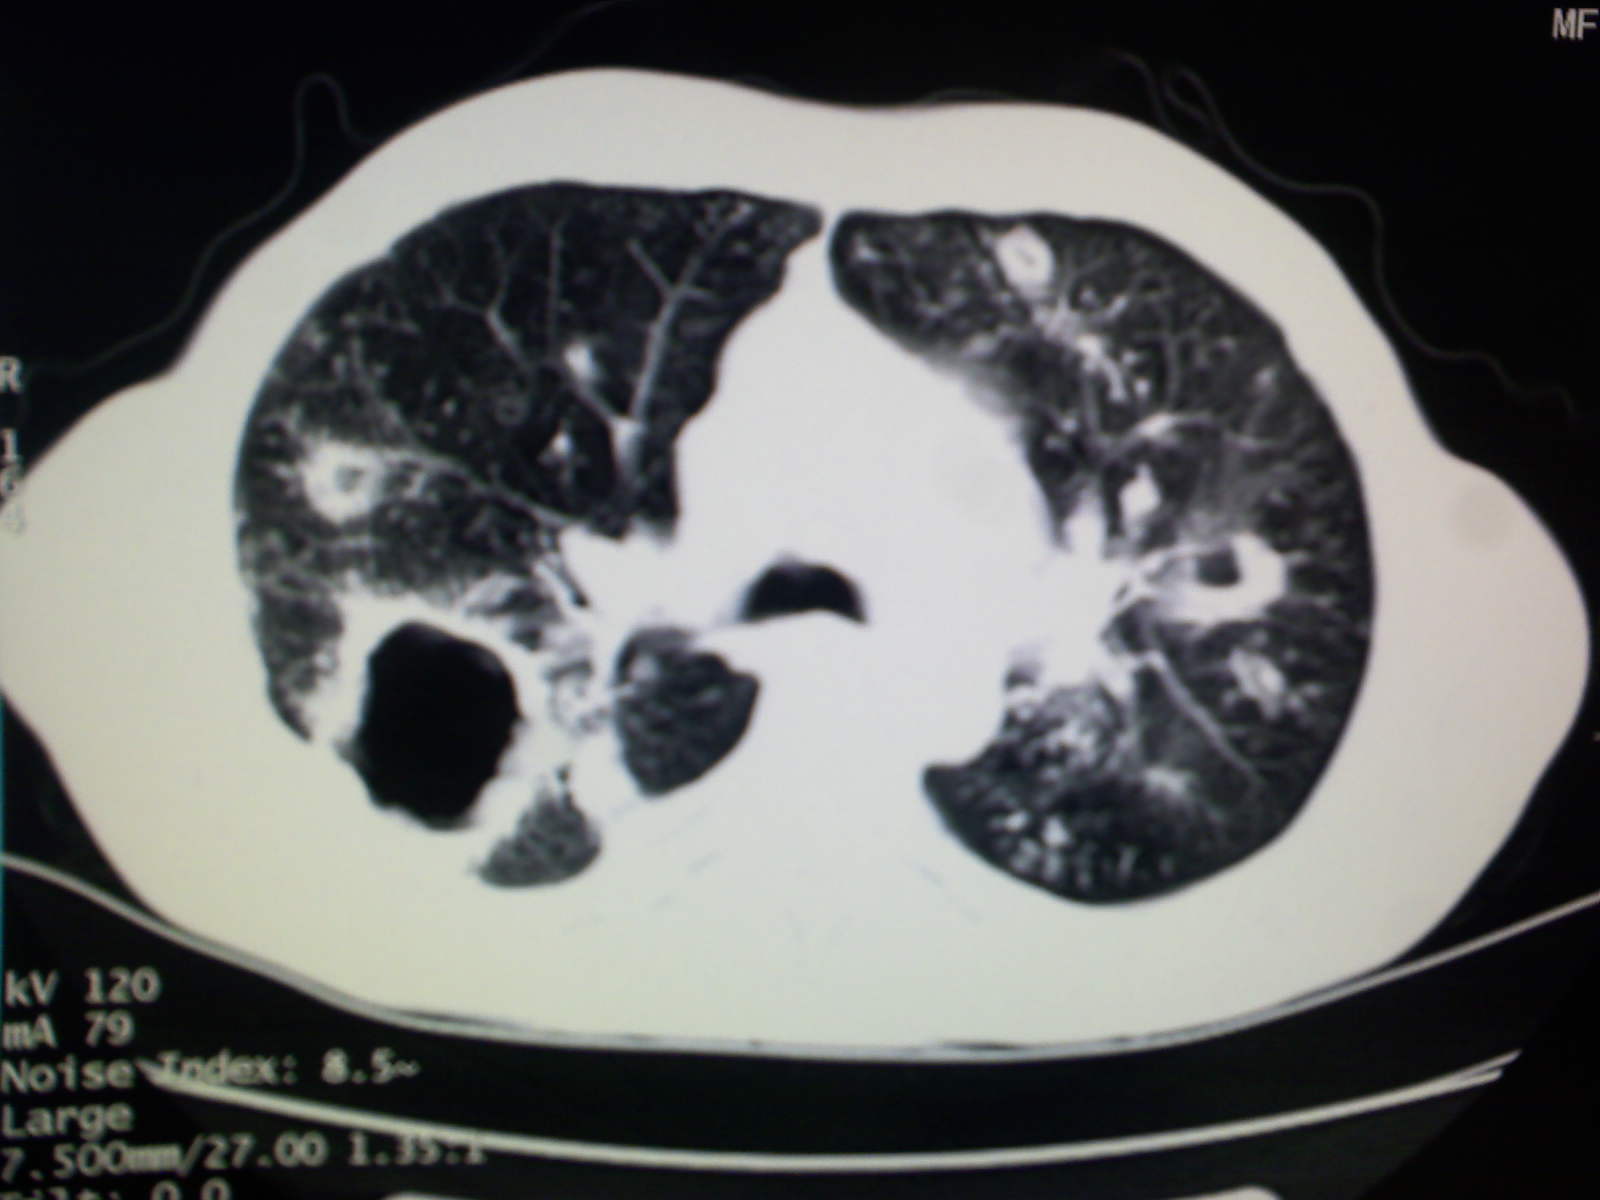

以下是引用卜一在2009-4-11 15:50:00的发言:[br]双肺继发性肺结核伴空洞形成,不排除合并霉菌感染!(病灶呈多形态 多特征 散在分布)。另:合并支气管扩张征伴感染!

以下是引用主力军在2009-4-11 15:55:00的发言:[br]两肺继发性肺结核可能性大。

以下是引用康鹏在2009-4-11 16:30:00的发言:[br]双肺继发性肺结核伴空洞形成合并感染[br]支气管扩张合并感染